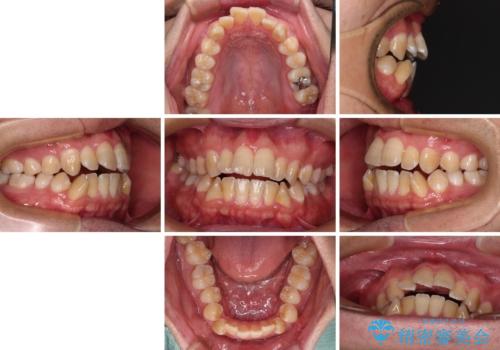

- 前歯の開咬を気にして来院された患者様です。

開咬の治療は、前歯を閉じるように動かすとともに、上下臼歯を圧下(骨内にめり込ませる)させることで進めて行きます。

インビザラインは臼歯の圧下を効果的に行えるため、インビザラインを用いて矯正治療を行うこととしました。